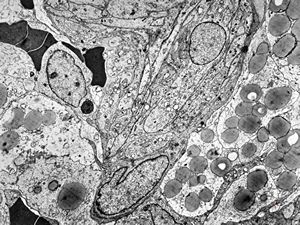

F,49y. | hemangioblastoma - brain

M,28y. | hemangioblastoma - brain